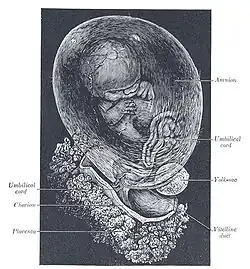

Formation of Placenta

As changes to the endometrium occur, cellular growth and the accumulation of glycogen cause fetal and maternal tissue to come together. This formation makes the functional unit called the placenta. The placenta does not mix blood between mother and fetus, but allows nutrients and waste products to diffuse between the two blood systems. The placenta provides protection by filtering out many harmful substances that the mother comes in contact with. The placenta cannot protect against some teratogens including but not limited to:

Amniotic Fluid

Attached to placenta is the membranous sac which surrounds and protects the embryo. This sac is called the amnion. It grows and begins to fill, mainly with water, around two weeks after fertilization. This liquid is called Amniotic fluid, it allows the fetus to move freely, without the walls of the uterus being too tight against its body. Buoyancy is also provided here for comfort. After a further 10 weeks the liquid contains proteins, carbohydrates, lipids and phospholipids, urea and electrolytes, all which aid in the growth of the fetus. In the late stages of gestation much of the amniotic fluid consists of fetal urine. The fetus swallows the fluid and then voids it to prepare its digestive organs for use after birth. The fetus also "breathes" the fluid to aid in lung growth and development.

- The embryo floats in a fluid filled bubble that will develop into the amniotic sac. The sac is covered by a protective layer of cells, called chorion. The yolk sac supplies the embryo with all its nutrients until the placenta is fully developed and takes over at around the twelfth week. During the first 12 weeks, the embryo will develop features and major organs of a human being. The embryo is susceptible to harmful environmental influences. This is a vital time for the embryo to develop healthily; taking supplements of folic acid, avoiding certain foods, and eliminating alcohol, cigarettes, and any unnecessary drugs or medicines.

- The fetal life-support system- the placental tissue that initially surrounds the fetus and the amniotic sac is becoming concentrated in one circular area on the womb wall to form the placenta.

Umbilical Cord

This is the life support for a growing embryo. The umbilical cord stretches between the placenta and the fetus. This cord contains the umbilical arteries and vein. The umbilical cord forms by week 5 of conception. The average cord is close to 22 inches long and may have the appearance of a coil. The umbilical cord is very rich in stem cells and is often used for parents who choose to store their stem cells in a blood bank or donate it to a blood bank. These stem cells can be used to treat over 45 disorders and is an alternative from extracting the stem cells from a donor.

- Umbilical Arteries

The exchange of gases, nutrients and oxygen takes place between the maternal blood and fetal blood. There are 2 main arteries.

- Umbilical Vein

Vein that carries nutrients and oxygen away from the placenta to the growing fetus. It also carries oxygen and nutrient rich blood. There is only 1 main vein.